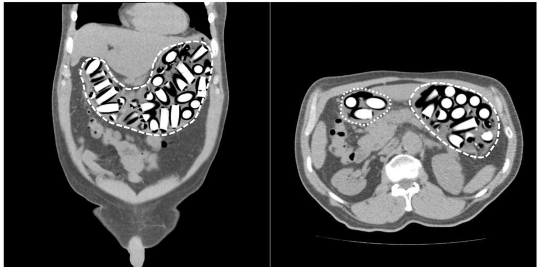

La radiografía de abdomen al ingreso mostró múltiples imágenes radiopacas en el marco cólico sugestivas de cuerpos extraños (Figura 1). Se solicitó una tomografía computarizada (TC) de abdomen con contraste en la cual se describieron hallazgos compatibles con síndrome pilórico secundario a retención gástrica de cuerpos extraños, sin evidencia de tránsito hacia distal (Figura 2). Fue llevado a laparotomía exploratoria identificando marcada distensión de la cámara gástrica; se realizó una gastrotomía y extracción sin complicaciones de 97 cuerpos extraños de látex en forma de dedo con pérdida del recubrimiento de parafina (Figura 3).

Figura 2. Tomografía computarizada contrastada de abdomen. A la izquierda (corte coronal) se observan imágenes hiperdensas cilíndricas sugestivas de cuerpos extraños en cámara gástrica (línea discontinua).

En caso de diagnóstico inconcluso con alta sospecha clínica, la TC de abdomen puede ser de gran utilidad con una sensibilidad y especificidad superiores al 95 % 5. La TC simple puede brindar más información, teniendo en cuenta que el medio de contraste puede interferir con la visualización de los paquetes 5,7. Dependiendo de la pureza del narcótico existen diferentes patrones de atenuación; la cocaína que constituye la sustancia más frecuentemente transportada, por lo general es isodensa con la materia fecal, mientras que la marihuana suele ser hiperdensa y la heroína hipodensa 5.